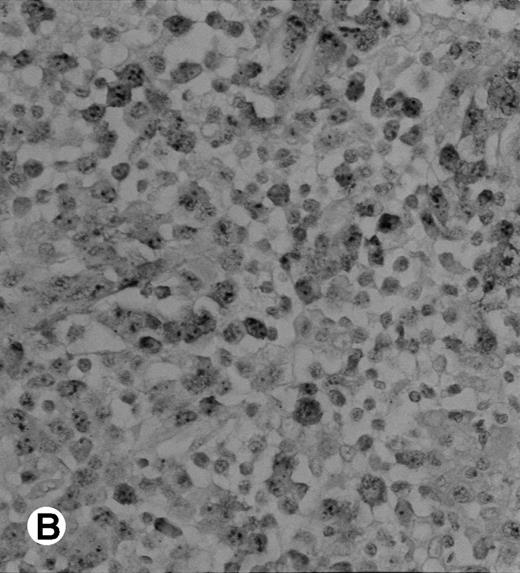

The polyclonal anti-p80 provided a staining of some large cells of 1 of the 11 LyP (case no. 4). A cytoplasmic staining of lymphomatous cells was also seen in 4 of the 15 CD30+ primary CTCL (cases no. 5, 6, 8, and 9) and in 3 of the 11 CD30+ secondary cutaneous lymphomas (cases no. 1, 2, and 3). Keratinocytes or dendritic cells of the dermis were sometimes stained by anti-p80. All p80+ cases were previously shown to contain NPM-ALK transcripts by nested RT-PCR. However, not all cases with NPM-ALK chimeric transcripts were stained by p80+. No p80+ cells were detected in MF and BID sections. The staining with the monoclonal ALK1 antibody was cytoplasmic and nucleolar and restricted to tumoral cells of CD30+lymphomas. Only 1 case of CD30+ primary CTCL was ALK1+ (case no. 8; Fig 3). This case was 1 of the 2 cases with a positive standard RT-PCR amplification, whereas the other 1 was found to be negative for both p80 and ALK1 immunostaining (case no. 10). The 3 cases of CD30+ secondary CTCL with NPM-ALK transcripts were stained for ALK1 (cases no. 1, 2, and 3; Fig 3). No ALK1-immunoreactive cell was found in LyP sections and no labeling of the epidermis was observed. None of the cases with a negative NPM-ALK detection by RT-PCR and none of the MF and BID was found to be stained for ALK1.

Immunohistochemical detection of chimeric NPM-ALK protein (×400). A case of CD30+ primary CLCL (case no. 8; A) and a case of CD30+ secondary CLCL (case no. 1; B) both with a positive NPM-ALK amplification by both RT-PCR and DNA-PCR were stained with the monoclonal ALK1 antibody. A granular cytoplasmic and strong nucleolar staining was observed on the large lymphomatous cells in these 2 cases.

Immunohistochemical detection of chimeric NPM-ALK protein (×400). A case of CD30+ primary CLCL (case no. 8; A) and a case of CD30+ secondary CLCL (case no. 1; B) both with a positive NPM-ALK amplification by both RT-PCR and DNA-PCR were stained with the monoclonal ALK1 antibody. A granular cytoplasmic and strong nucleolar staining was observed on the large lymphomatous cells in these 2 cases.